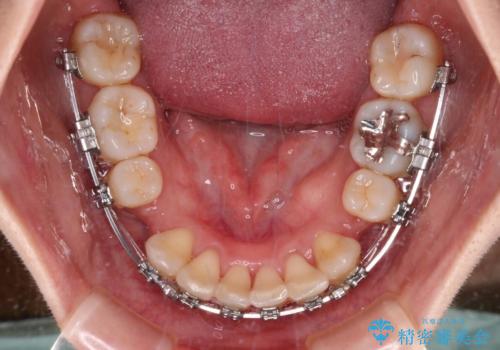

- 矯正装置

- メタルブラケット

横から見た際の口元の飛び出した印象も改善したいとのことで、上下左右の第一小臼歯4本を抜歯し、ワイヤー装置にて抜歯矯正を行うこととしました。

順調に歯が動き、補綴治療も含め2年弱で治療を終えることができました。